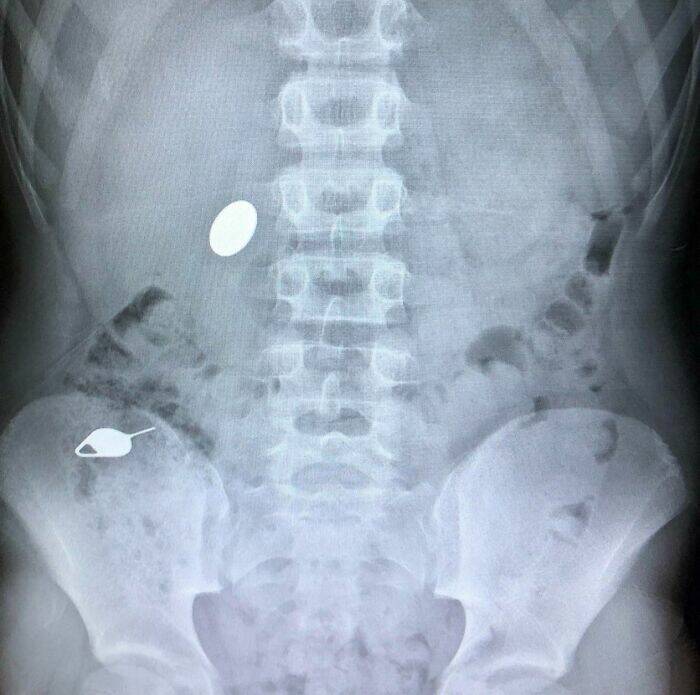

My Kid Swallowed A Penny While Showing His Little Brother How He Accidentally Swallowed A Sim Key The Day Before